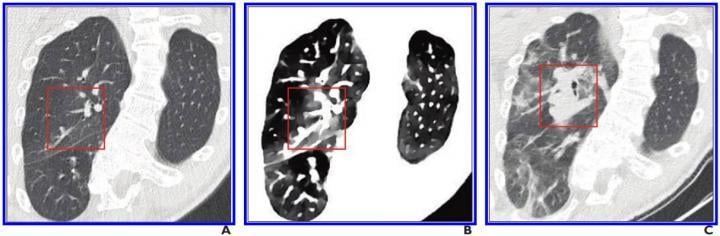

This photo gallery shows the variety of radiological presentations of COVID-19 (SARS-CoV-2) in medical imaging, including computed tomography (CT), radiograph X-rays, ultrasound, echocardiograms and magnetic resonance imaging (MRI). The radiology images show examples of typical COVID pneumonia in the lungs and the numerous complications the virus causes in the body in multiple organs, including the brain, kidneys, heart, abdomen and vascular system.